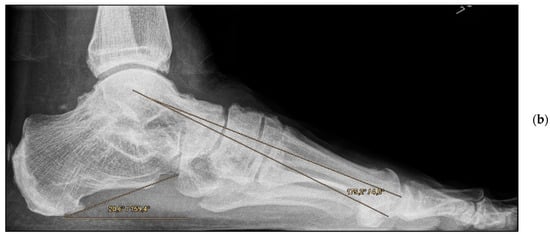

Figure 2.

Pre- and post-operative radiographic findings of combined talonavicular arthrodesis and calcaneal displacement osteotomy, left foot. (a) Anteroposterior view pre-operative, (b) anteroposterior view post-operative.

Figure 3.

Pre- and post-operative radiographic findings of combined talonavicular arthrodesis and calcaneal displacement osteotomy, left foot. (a) Lateral view pre-operative, (b) lateral view post-operative.